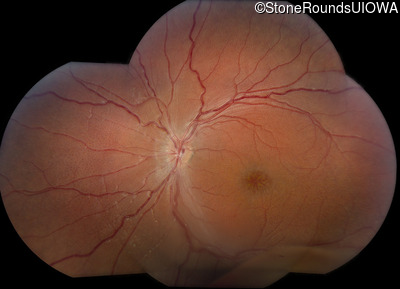

XL Retinoschisis (IIIB1)

Age at visit: 6 years

This 6 year old boy began sitting very close to the television at age 2.

XL Retinoschisis RS1 Tyr93Stop TAT>TAG   XL